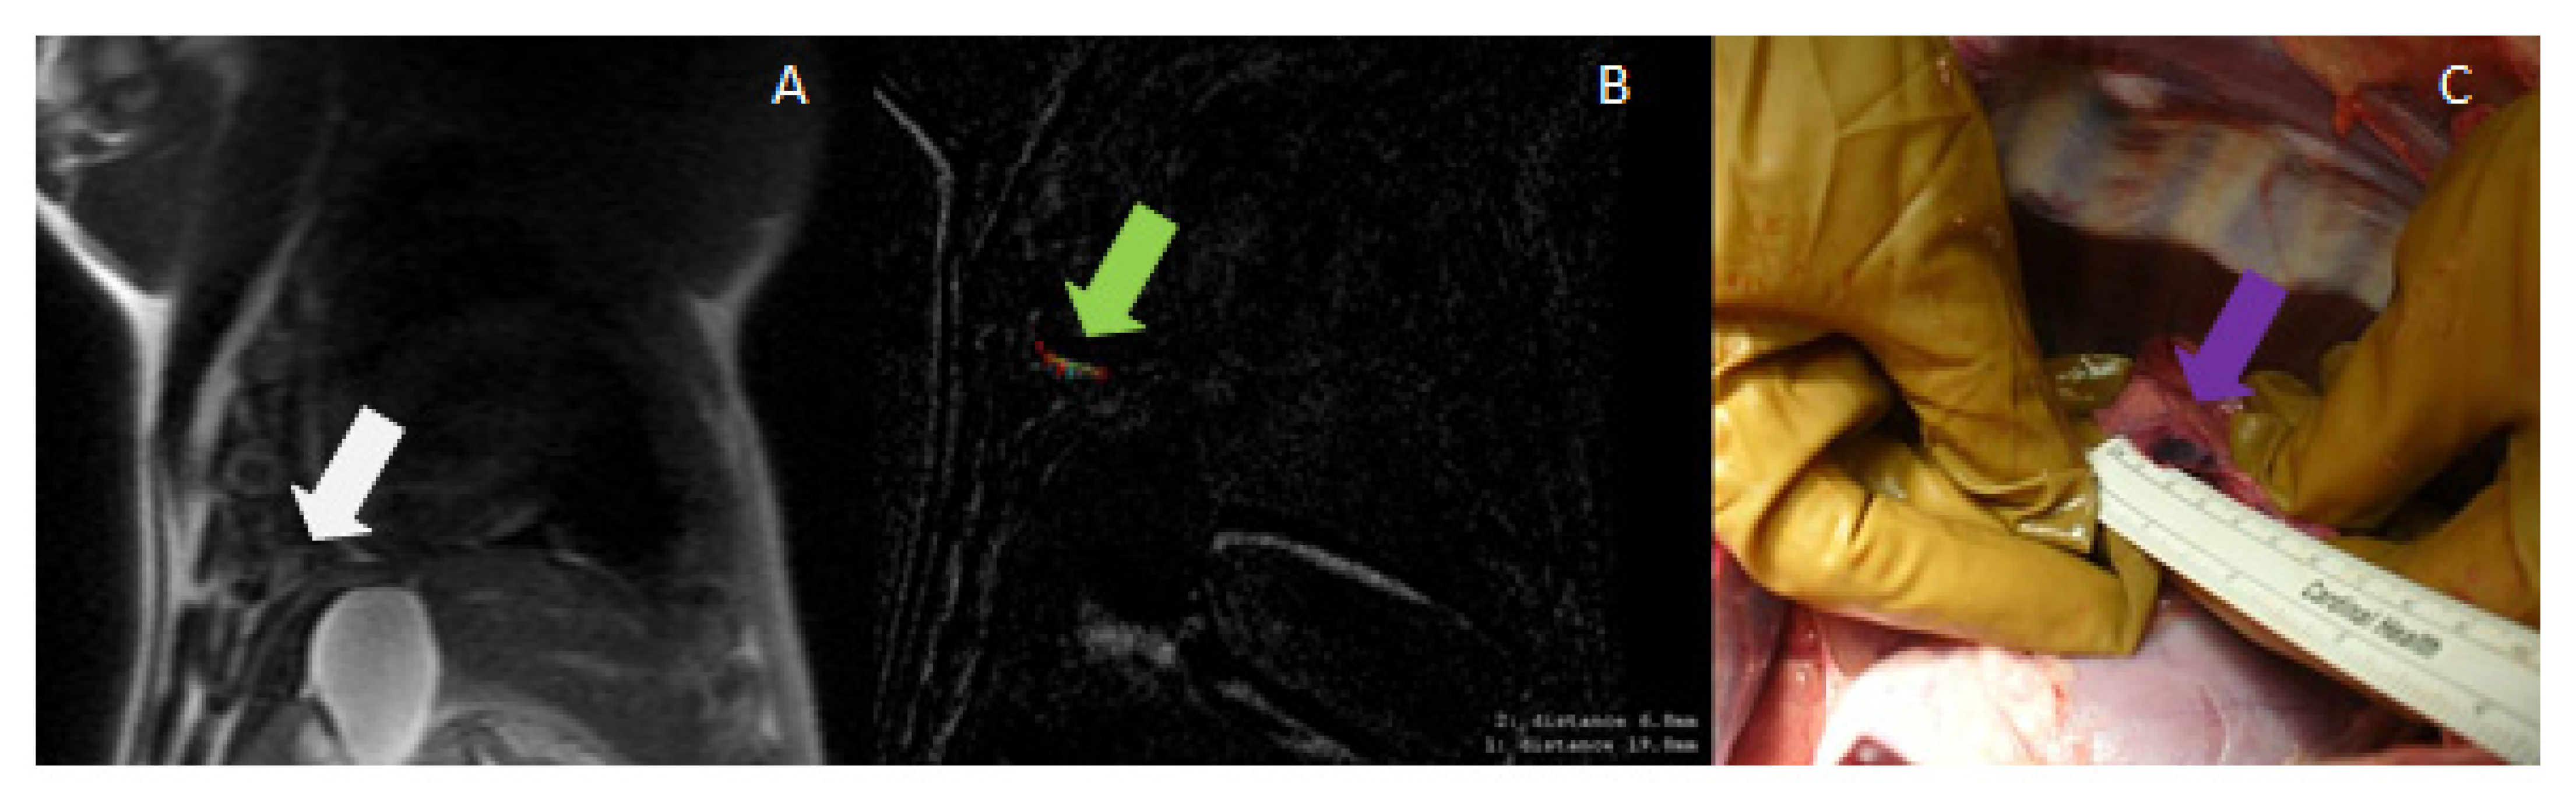

3.2. Radiofrequency Ablation

3.3. Magnetic-Resonance-Guided Focused Ultrasound